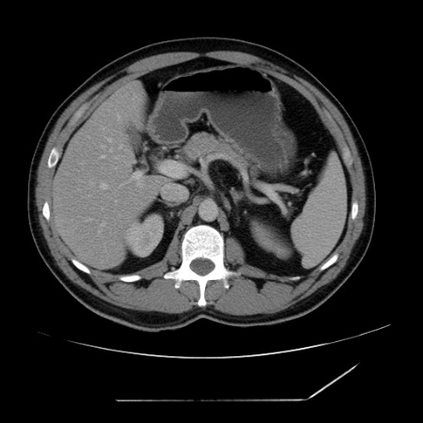

Integrating high-level semantically correlated contents and low-level anatomical features is of central importance in medical image segmentation. Towards this end, recent deep learning-based medical segmentation methods have shown great promise in better modeling such information. However, convolution operators for medical segmentation typically operate on regular grids, which inherently blur the high-frequency regions, i.e., boundary regions. In this work, we propose MORSE, a generic implicit neural rendering framework designed at an anatomical level to assist learning in medical image segmentation. Our method is motivated by the fact that implicit neural representation has been shown to be more effective in fitting complex signals and solving computer graphics problems than discrete grid-based representation. The core of our approach is to formulate medical image segmentation as a rendering problem in an end-to-end manner. Specifically, we continuously align the coarse segmentation prediction with the ambiguous coordinate-based point representations and aggregate these features to adaptively refine the boundary region. To parallelly optimize multi-scale pixel-level features, we leverage the idea from Mixture-of-Expert (MoE) to design and train our MORSE with a stochastic gating mechanism. Our experiments demonstrate that MORSE can work well with different medical segmentation backbones, consistently achieving competitive performance improvements in both 2D and 3D supervised medical segmentation methods. We also theoretically analyze the superiority of MORSE.